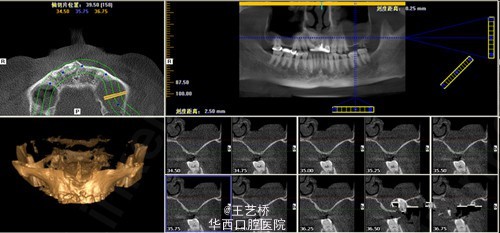

各式各样形态的上颌窦(二)

接着之前放图